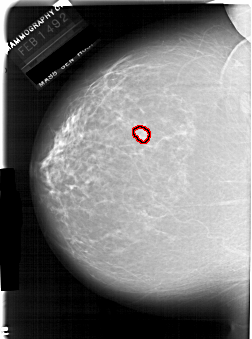

FILE: A_1940_1.LEFT_CC.OVERLAY

TOTAL_ABNORMALITIES 1

ABNORMALITY 1

LESION_TYPE MASS SHAPE LOBULATED MARGINS CIRCUMSCRIBED

ASSESSMENT 3

SUBTLETY 4

PATHOLOGY BENIGN

TOTAL_OUTLINES 1

BOUNDARY